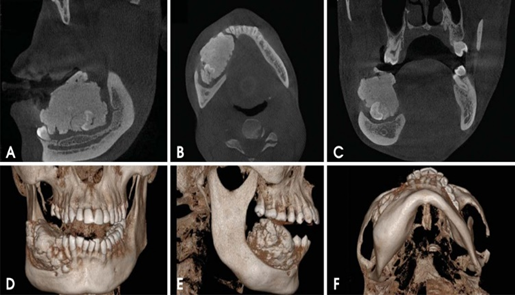

- Trường hợp 2: Bệnh nhân nữ, 75 tuổi đến khám với lý do khối sưng vùng vòm khẩu cái cách đây hơn 01 năm, nay kích thước lớn dần nên vào viện. Thăm khám lâm sàng thấy vòm khẩu cái tương ứng vùng răng 11, 12 có khối sưng, mật độ mềm, có dấu bóng nhựa, giới hạn không rõ, ấn đau nhức. Nướu quanh răng 11, 12 viêm đỏ. Bệnh nhân được chụp phim XQ răng toàn cảnh thường qui để kiểm tra thấy hình ảnh thấu quang rộng từ vùng chân răng 13 đến răng 21. Bệnh nhân được chụp tiếp Cone Beam CT, qua các lớp cắt đã thấy rõ hình ảnh có có răng mọc ngầm lệch hoàn toàn trong xương vùng chân răng 11, 12, 13 và 22, hình ảnh thấu quang rộng từ vùng chân răng 13 đến răng 21, kích thước khoảng 3x3cm. Bác sỹ điều trị lập kế hoạch cụ thể phẫu thuật nạo nang lấy bỏ răng ngầm.